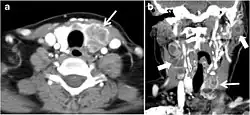

Fig. 13. A 27-year-old female patient known to have goiter. a, b Axial and sagittal enhanced CT scan images of the neck demonstrate a heterogeneously enhancing, enlarged thyroid gland with scattered calcifications (white arrow), cystic changes, and substantial retro-sternal extension (black asterisks). No lymphadenopathy or substantial airway narrowing.[1] -

Fig. 14. A 19-year-old male patient known to have multi-nodular goiter and FNA, showing underlying Hashimoto's thyroiditis. a, b Sagittal and transverse greyscale and colour Doppler ultrasound of the neck demonstrate a hypoechoic enlarged right thyroid lobe with small hyperechoic regenerative nodules and marked hypervascularity (white arrows). c, d Enhanced axial CT scan images of the neck demonstrate a heterogeneously enhancing and enlarged thyroid gland, left more than right lobe, and the trachea is markedly narrowed.[1] -